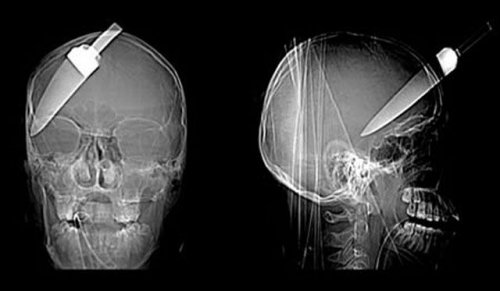

16-летний подросток обманул смерть, когда ему в голову вонзили 12-сантиметровый нож. Подростка отвезли в больницу с кухонным ножом, торчащим из его лба.